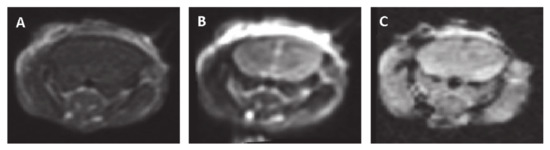

Figure 6.

Representative MRI slices obtained 48 h post-pulsed electrical fields (PEFs) application (100 pulses at 300 V) (A). Contrast-enhanced T1-MRI. (B) T2-MRI. (C) Gradient echo (GE) MRI.